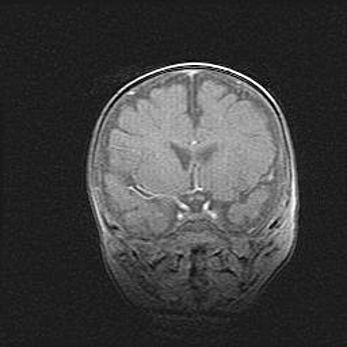

Наружная гидроцефалия с возможной атрофией височных областей.

Возраст: 28 дней

Вес: 3670 г

Пол: мужской

Окружность головы: 38 см

Срок гестации: 40 недель

Гидроцефалия головного мозга у новорожденных – это заболевание, которое характеризуется скоплением избыточного количества спинномозговой жидкости в желудочковой системе головного мозга в результате затруднения её перемещения от места выработки к месту поглощения в кровеносную систему или вследствие нарушения абсорбции. При открытой наружной форме гидроцефалии у новорожденных расширяются и переполняются субарахноидные пространства.

При нормотензивных  формах,  которые,  как  правило,  являются  следствием  перенесенных ишемических  повреждений  паренхимы  мозга,  возможно  сочетание микроцефалии  с нормотензивной гидроцефалией. В основе данных изменений лежит атрофия больших полушарий с преимущественной  локализацией  в  лобно-височных  областях.